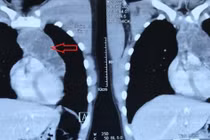

Bệnh viện Nhân dân 115 TP HCM cho hay vừa phẫu thuật lấy khối u trung thất thành công cho anh N.N.N (20 tuổi, ngụ Đồng Nai). Anh N. tiền căn chưa ghi nhận bệnh lý bất thường, gần đây cảm thấy nhói ngực, nhất là khi ho, đi khám tại phòng khám tư, siêu âm phát hiện có khối u trong ngực.

Nhập viện Bệnh viện Nhân dân 115, bác sĩ chỉ ghi nhận bệnh nhân than đau ngực nhẹ, ngoài ra không có triệu chứng gì bất thường. Qua CT scan ngực vùng trung thất cho thấy hình dạng khối u kích thước khoảng 8.5 x 8 x 6 cm. Các bác sĩ tiến hành mở ngực trái và bóc ra khối u to có kích thước 10x10 cm, nặng 1 kg, xâm lấn, chèn ép động mạch chủ, tĩnh mạch chủ.